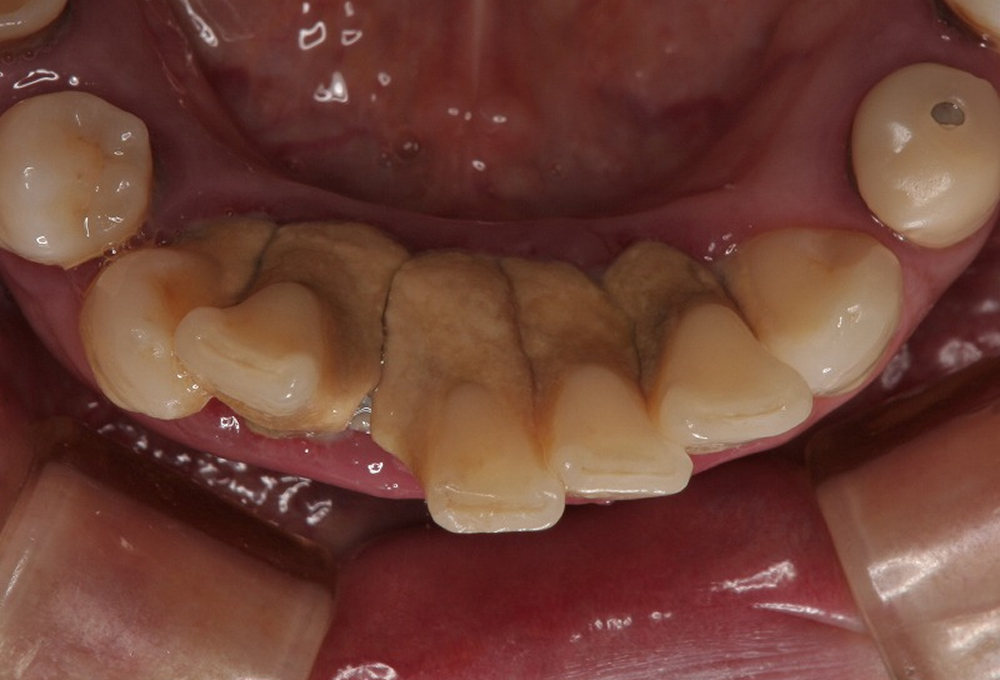

③術前 下顎